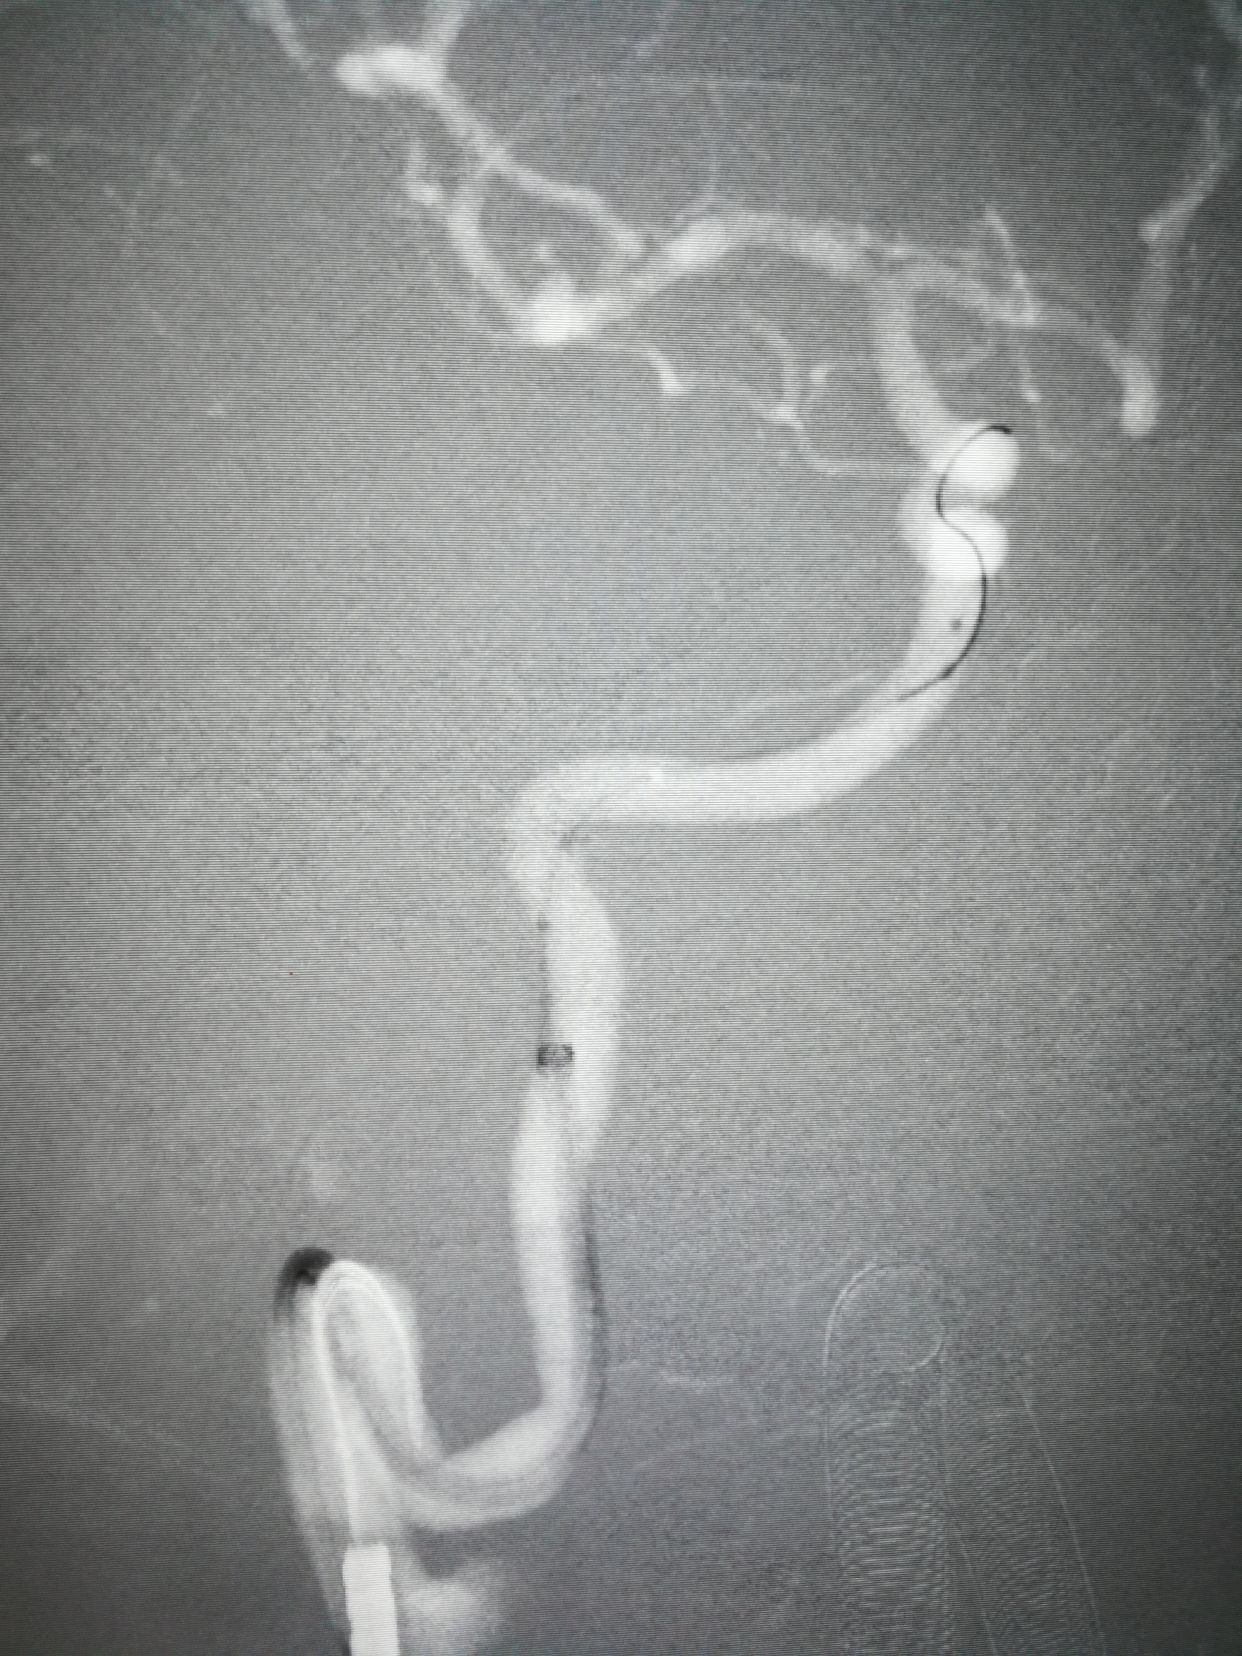

CTA示右侧大脑中分叉部动脉瘤,瘤子小,颈宽,主要累及下干,颈内动脉预期

术前3d和工作位